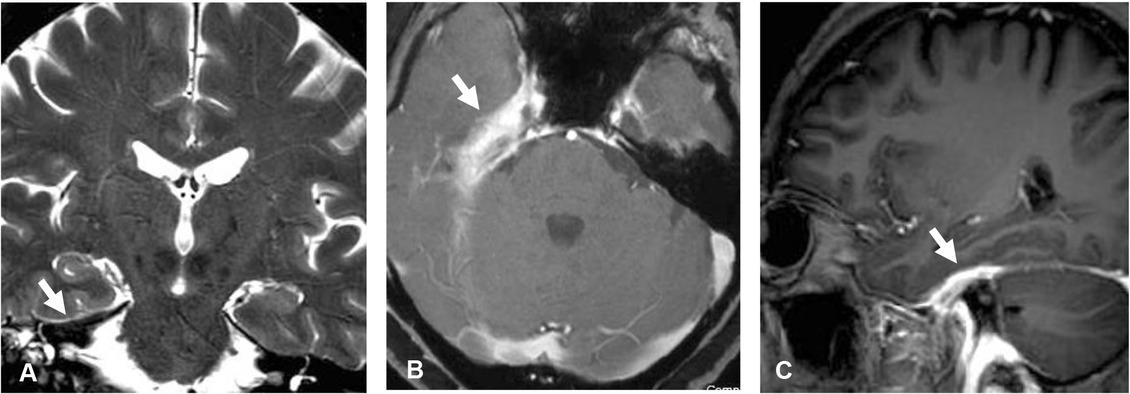

Figure 2